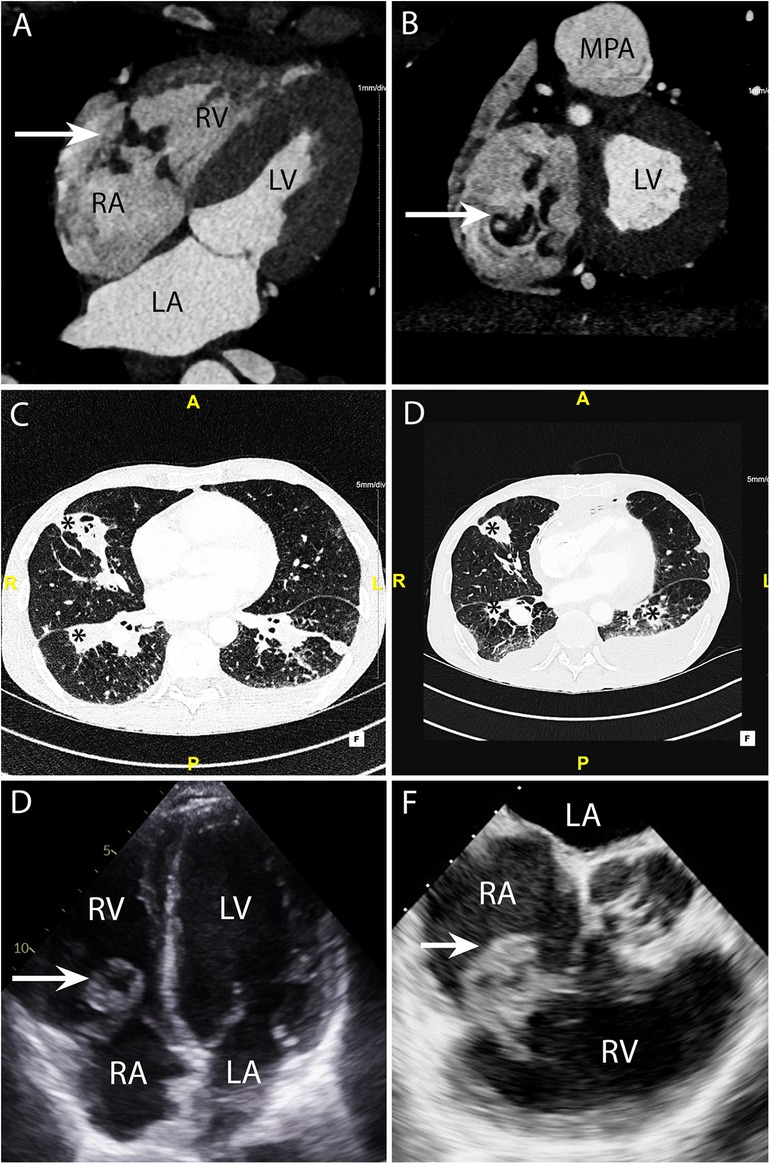

Figure 5. CASE 5 - A 53-year-old man presented with fever, dyspnoea and confusion on a backgound history of intravenous drug use. Blood cultures grew Staphylococcus aureus (see text). RA, right atrium; RV, right ventricle; MPA, mean pulmonary artery; LA, left atrium; LV, left ventricle.

A 53-year-old man presented with fever, dyspnoea and confusion on a backgound history of intravenous drug use. Blood cultures grew Staphylococcus aureus. CT brain imaging showed a subarachnoid haemorrhage. Cardiac CT was performed: Axial 4-chamber (Figure 5A) and oblique coronal (Figure 5B) views showed a low density soft tissue vegetation (arrow) (HU 59) attached to the tricuspid valve leaflets with an associated perforation (arrow) over the posterior tricuspid valve leaflet (Figure 5B). The wide field of view reconstructions (Figures 5C and 5D) showed bilateral foci of cavitating consolidation consistent with septic emboli (asterisks). Prior to CT, a TTE and TOE were performed. TTE 4-chamber (Figure 5E) and TOE ME AV SAX (Figure 5F) views demonstrated a large mobile heterogenous mass consistent with a large vegetation. A cardiac CT and a flash ECG-gated aorta were arranged to further elucidate leaflet morphology, assess for extra-cardiac complications and evaluate the coronary arteries prior to surgical intervention.